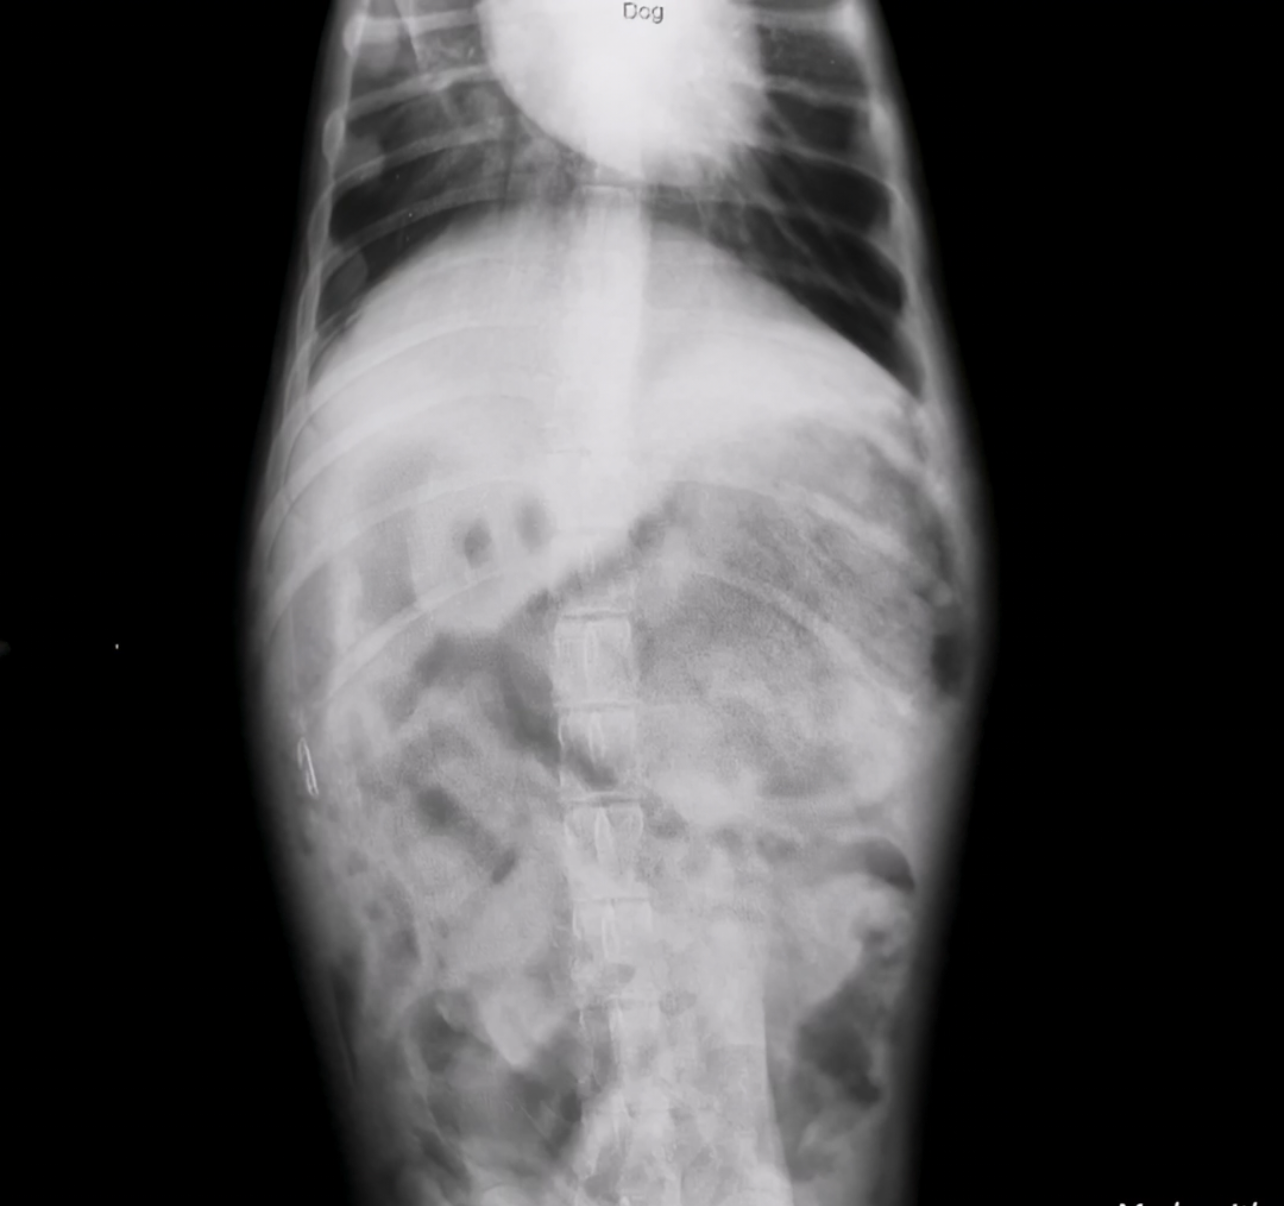

• Abdominal Radiographs:

Revealed a distended stomach with soft-tissue opacity suggestive of a foreign body

Gastric Foreign body in a 4 months puppy

Xtray show abnormal large gastric content